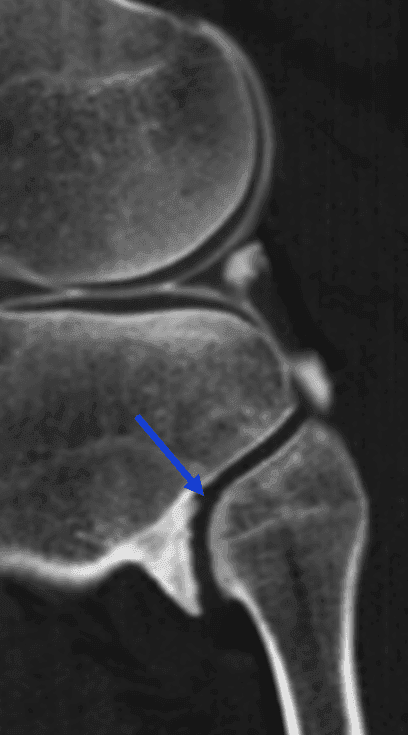

Notez par ailleurs l'arthropathie mécanique tibio-fibulaire proximale avec ostéophytose marginale (flèches bleues).

Sagittal arthroscanner